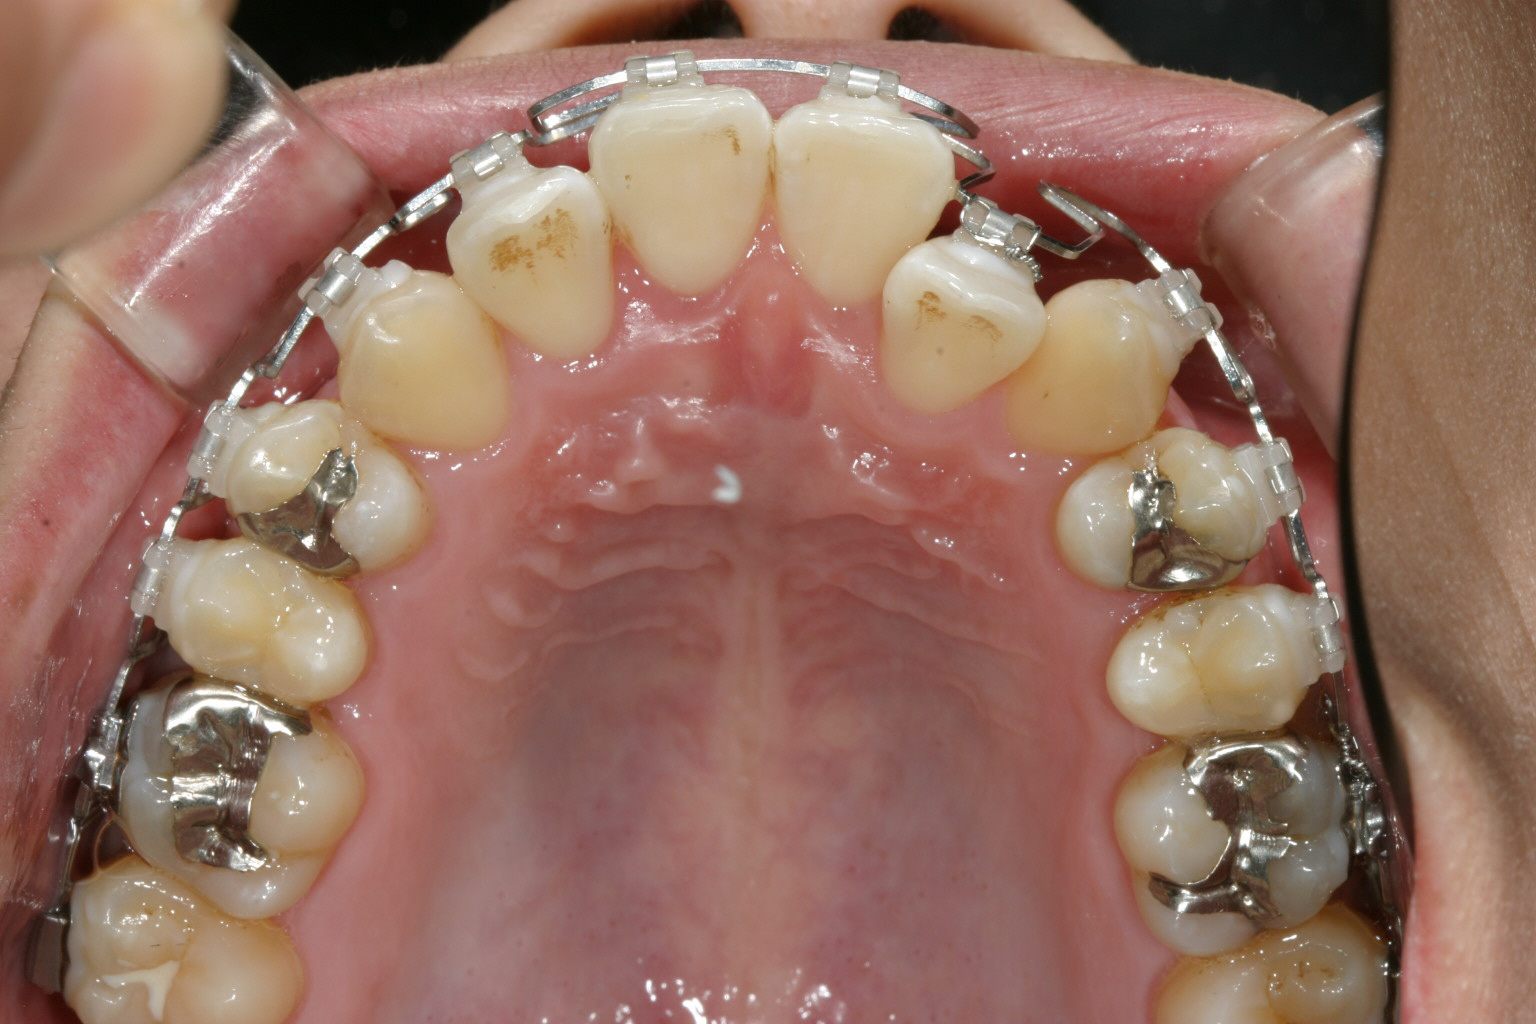

前歯がすご出て又犬歯も飛び出しています。

下顎もアーチが狭い為にガタガタしています。